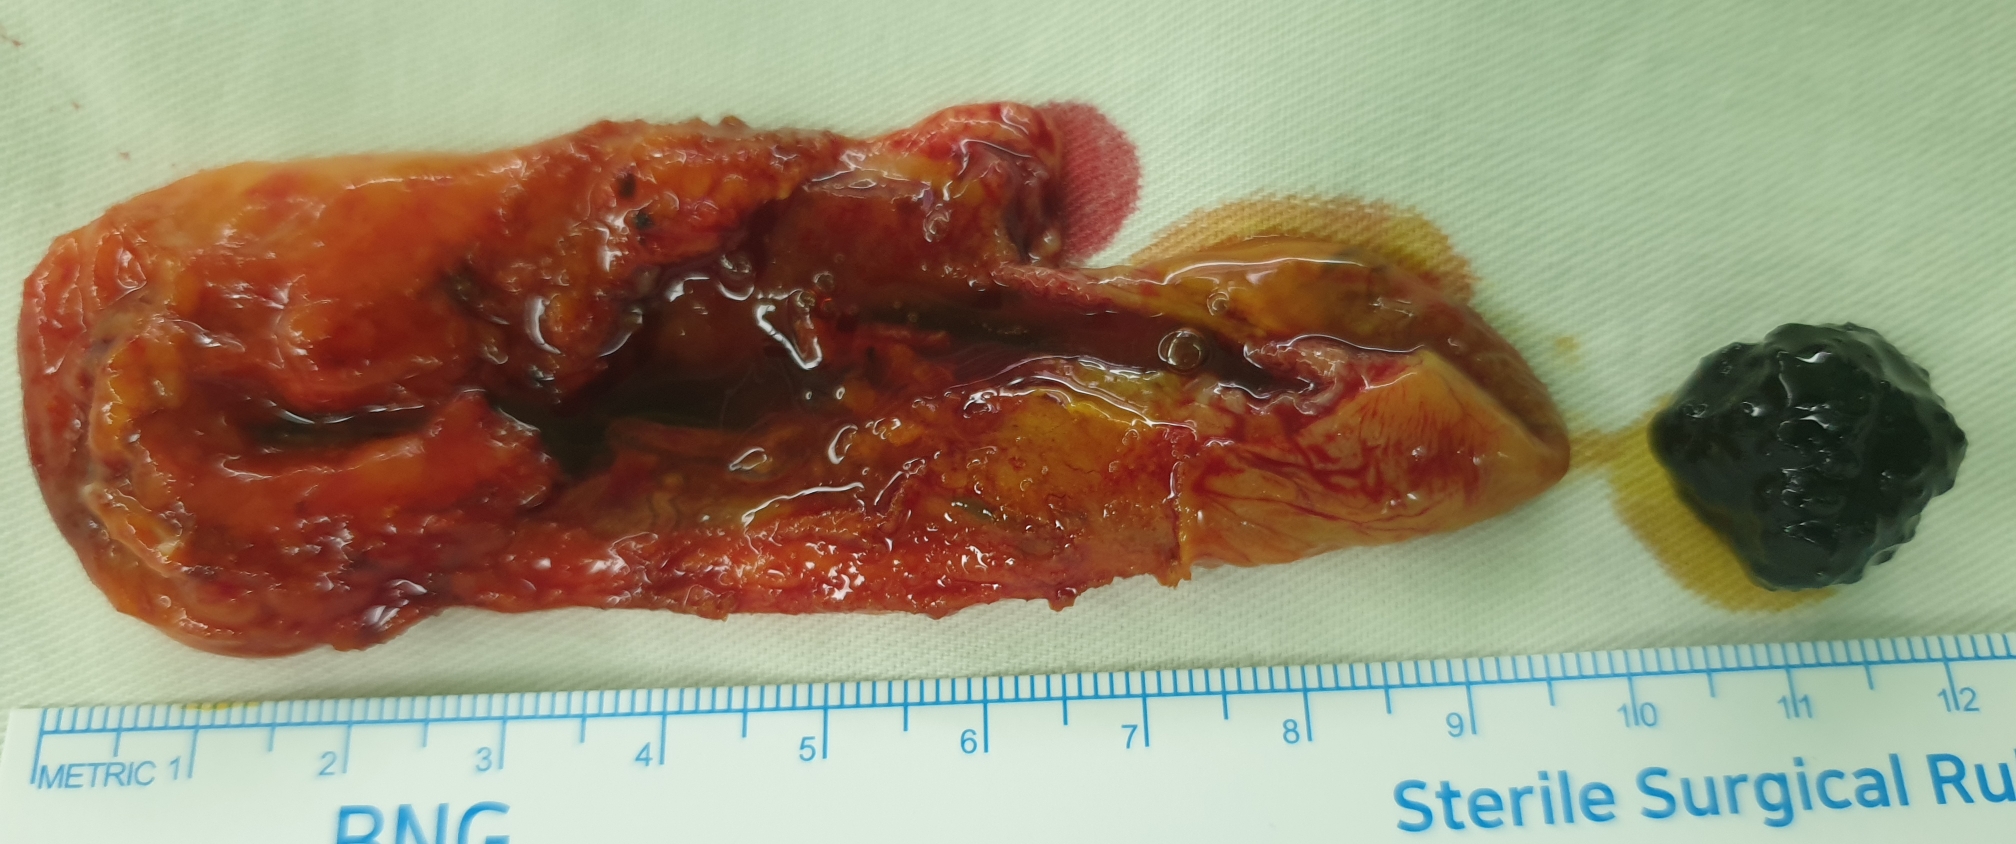

복강경 담낭절제술을 시행했습니다.

수술은 잘 끝났고 15분 걸렸습니다.